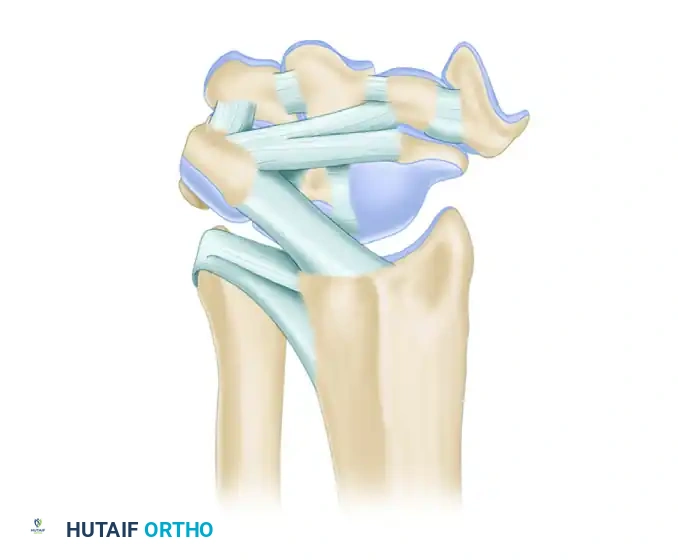

Carpal Ligamentous Architecture

Carpal stability relies entirely on its complex ligamentous network, divided into intrinsic (interosseous) and extrinsic (capsular) ligaments.

Palmar (Volar) Ligaments

Palmar ligaments are thicker and mechanically stronger than their dorsal counterparts. They form a double-V configuration that guides carpal kinematics and prevents volar intercalated segment instability (VISI) or dorsal intercalated segment instability (DISI).

Extrinsic Palmar Ligaments:

* Radioscaphocapitate (RSC): Acts as a fulcrum for scaphoid flexion.

* Long Radioscapholunate (LRSL): Primarily a neurovascular conduit rather than a mechanical stabilizer.

* Short Radiolunate (SRL): Primary stabilizer of the lunate to the radius.

Intrinsic Palmar Ligaments:

* Scapholunate (SL) Interosseous Ligament: The dorsal band is the thickest and most critical for stability.

* Lunotriquetral (LT) Interosseous Ligament: The volar band is the thickest and most critical for stability.

Dorsal Ligaments

Dorsal ligaments are thinner but crucial for preventing dorsal carpal subluxation. They are categorized by their morphological variations.

Dorsal Radiocarpal Ligaments (Four Types):

Dorsal Intercarpal Ligaments (Three Types):

Comprehensive Dorsal Perspective:

The dorsal intercarpal (DIC) and dorsal radiocarpal (DRC) ligaments form a horizontal "V" that stabilizes the proximal row during wrist flexion.